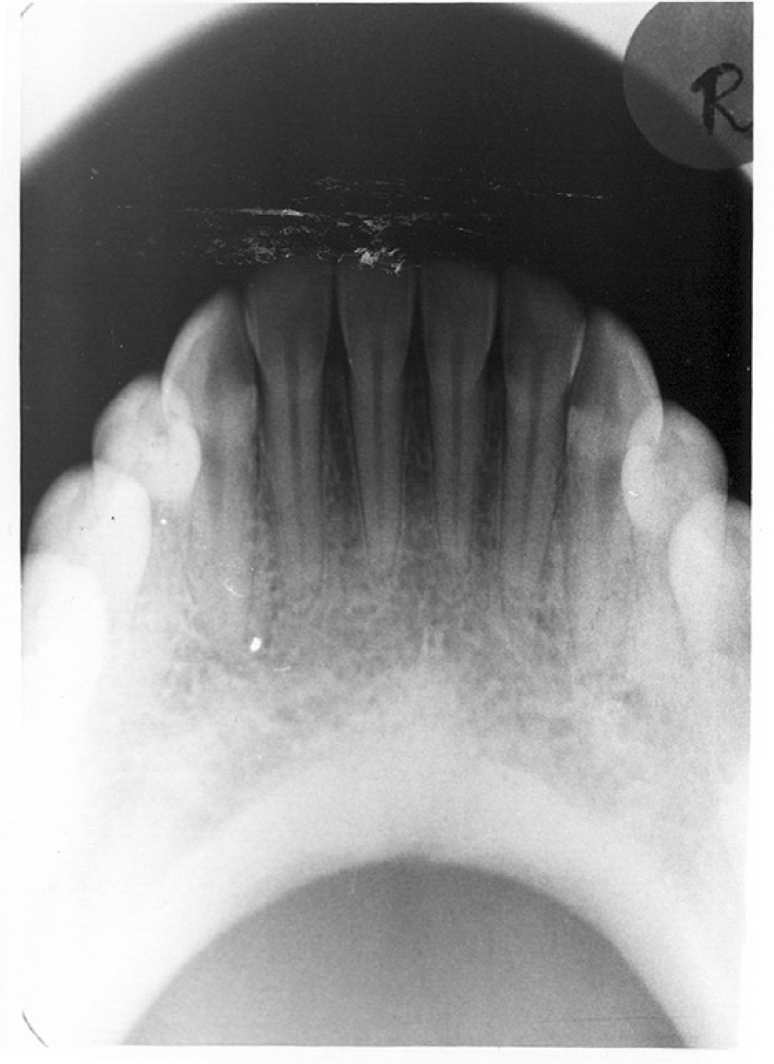

Figure 2 - Bitewing Images

Figure 2

Bitewing examinations were introduced by Dr. Raper in 1925. Bitewing images focus on the clinical crowns of both the maxillary and mandibular teeth. Bitewings do not show the apices of the tooth and cannot be used to diagnose in this area. The greatest value of bitewing radio- graphic images is the detection of interproximal caries in the early stages of development, before it is clinically apparent. The arrows in Figure 2 indicate areas of interproximal caries. Bitewing images also reveal the size of the pulp chamber and the relative extent to which proximal caries have penetrated.